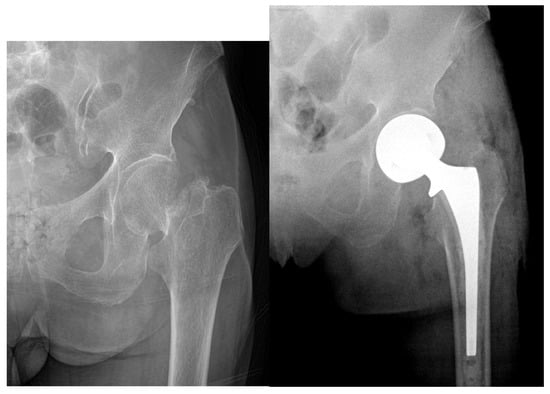

2.4. Displaced Femoral Neck Fractures: Hemiarthroplasty vs. Total Hip Arthroplasty